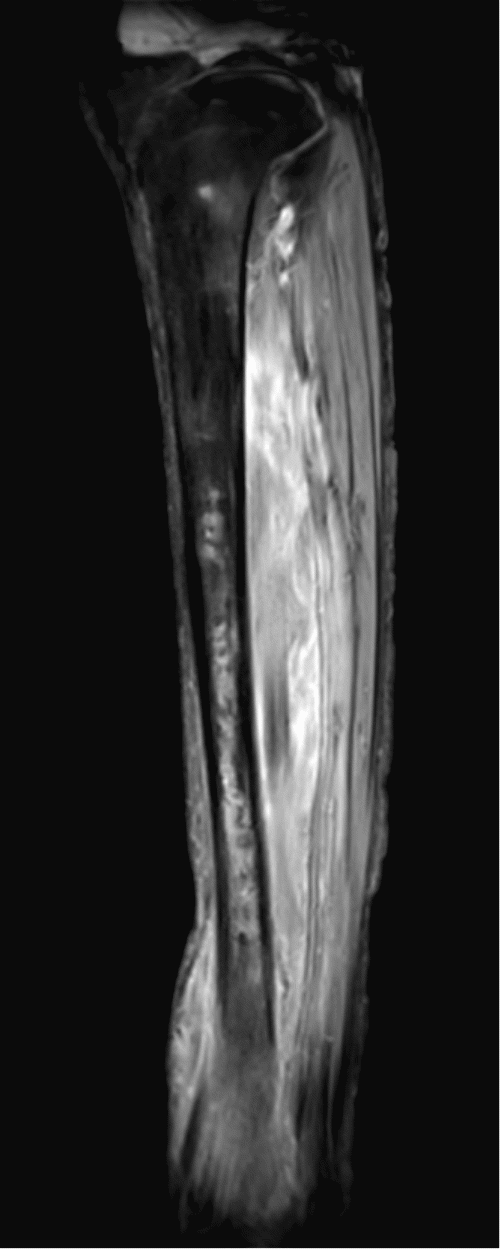

Magnetic resonance imaging (MRI) of the right lower extremity showed findings consistent with noninfectious osteomyelitis—diffuse soft tissue edema around the right ankle with effusion, fluid in the posterior tibialis tendon sheath with synovial and muscle enhancement, and osseous hyperenhancement of the mid-tibial shaft with periosteal edema (Figure 2). Computerized tomography (CT) scan of the abdomen and pelvis with IV contrast was notable for soft tissue stranding around the pancreatic head, a large pancreatolith in the body of the pancreas, and a non-occlusive superior mesenteric vein (SMV) thrombus (Figure 3). MRI of the abdomen demonstrated pancreatic ductal dilation and a focal area of pancreatic necrosis in the uncinate directly adjacent to the SMV (Figure 4).

Figure 2. CT Scans. Published with Permission

A.

A) Axial T1 MRI

B.

B) axial T2 fat-suppressed MRI through the distal lower leg showing bone marrow edema in the tibia but not the fibula, soft tissue edema surrounding the tibia, and periosteal new bone along the lateral aspect of the tibia

C.

C) Coronal STIR MRI showing distal tibial bone marrow edema and extensive intramuscular and subcutaneous edema

D.

D) Sagittal T1 fat-suppressed gadolinium-enhanced MRI showing heterogeneous distal tibial bone marrow enhancement and diffuse intramuscular enhancement